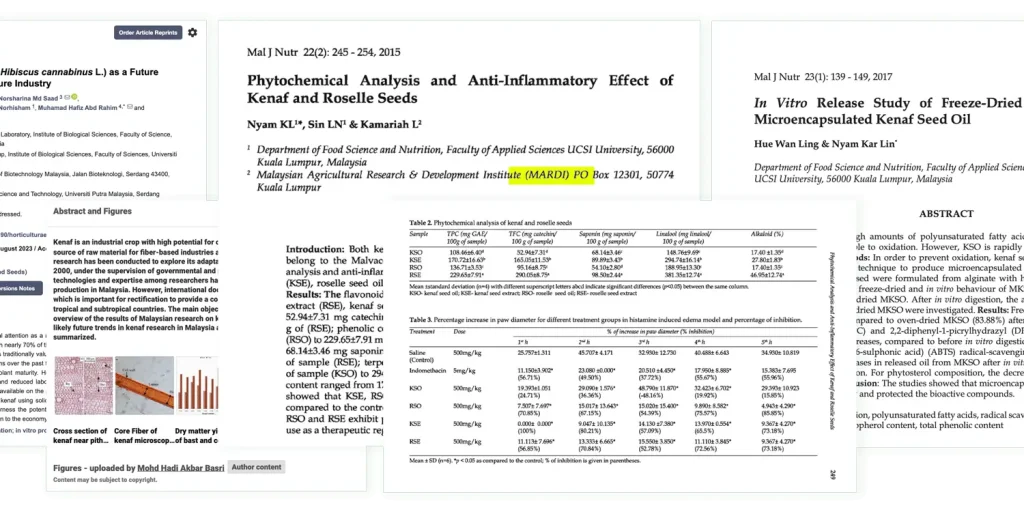

Banyak Kajian Dalam Negara Juga Sahkan Ekstrak Kenaf Mujarab Hilangkan Sakit Radang Akibat Obesiti dan Kolesterol.